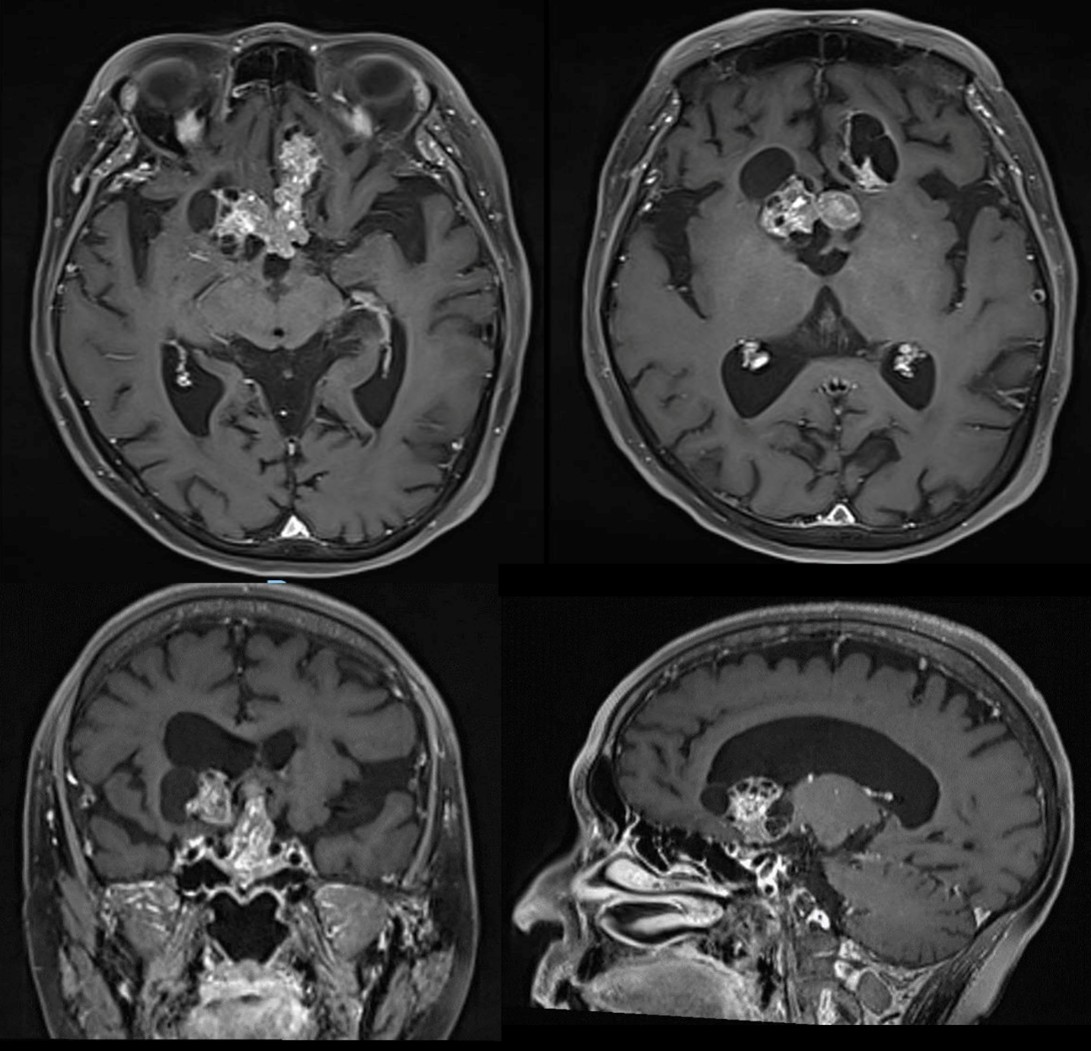

MRI with contrast confirmed tumor recurrence finding a predominantly suprasellar solid tumor significantly shifting upwards the third ventricle with anteriorly extension to the basal frontal gyrus in the anterior cranial fossa and a lateral cystic component (Figure 1). Surgical transcranial resection was decided.